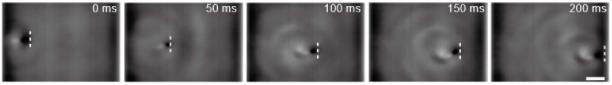

由于微型机器人在人体内的成像和导航是无线医疗机器人临床应用中的一个关键挑战,研究人员使用了超声设备,将磁驱软体鱼放置在血管模型内,使用超声设备对软体鱼进行成像和监测,并由频率为30赫兹、振荡角度为30°的振荡磁场驱动。

从下图可以看出,磁驱软体鱼可以在超声成像下游过血管。

超声波引导磁驱软体鱼运动。